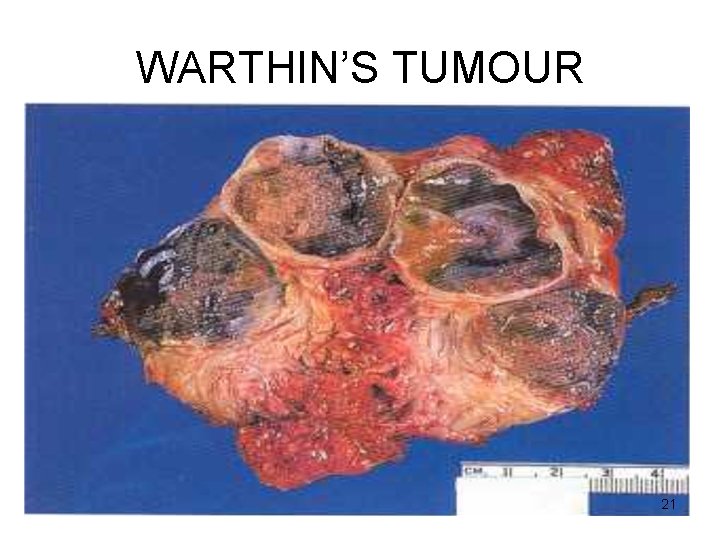

WARTHIN’S TUMOUR Gross • Encapsulated • Cut surface : pale-grey narrow cystic / cleft-like / convoluted spaces contain serous / mucinous fluid 20

WARTHIN’S TUMOUR 21